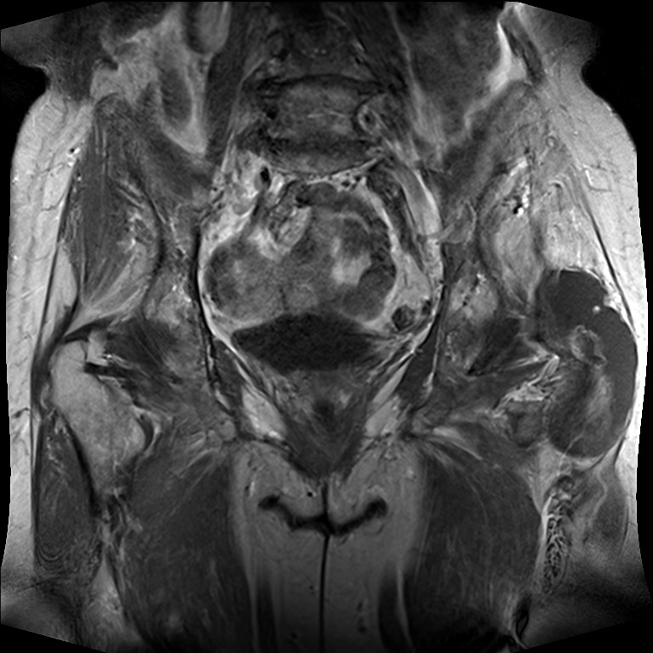

Lateral to the greater trochanter in the bursa trochanterica there was evidence of fluid showing homogeneous hyperintensity without sedimentation in fluid-sensitive sequences. Proton-weighted imaging revealed two nodular wall extensions in teardrop shape extending craniolaterally. These extensions measured a maximum of 1 cm at the base. In addition, at the roof of the fluid-filled cavity there was a space measuring approximately 1.5 x 0.5 cm. In the native fat-suppressed T1 turbospinecho sequence, this space-occupying lesion was partially hyperintense. This was considered to be hemosiderin. After application of gadolinium, there was a vigorous enhancement of the lining of the height. In addition, there was diffuse enhancement of the muscles in the immediate vicinity of the bursa. The hemorrhaged mass showed no enhancement of the contrast medium. In summary, the recent MRI exhibited an enlarged trochanteric bursitis with some intrabursal soft tissue formation suspicious for pigmented villo-nodular synovitis (PVNS) of the bursa trochanteric (PVNSBT) (Figure 1 [Fig. 1], Figure 2 [Fig. 2], Figure 3 [Fig. 3], Figure 4 [Fig. 4]).

Figure 1: Proton-weighted coronal plane showing an enlarged bursa trochanterica on the left side

Figure 4: T-1 native coronal plane exhibiting the enlarged bursa trochanteria containing PVNS-soft-tissue